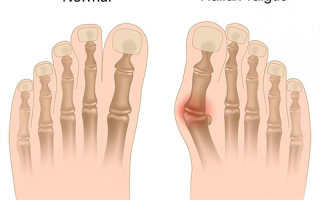

Hallux valgus – это патология с выдвижением большого пальца стопы в плюснефаланговом суставе. Палец отходит кнаружи под углом по состоянию к остальным. Пациентки женского пола болеют чаще, примерно в 10 раз. Редко, но наблюдается в детском возрасте.

Важную роль в развитии патологического процесса играет неровное мышечное натяжение, обеспечивающее приведение и отведение пальца. При формировании экзостоза мышечный дисбаланс обостряется, плюснефаланговый сустав теряет стабильность. Нарост является следствием постоянного нажима обуви на боковую поверхность. Давление перераспределяется на головки III и II плюсневых костей, которые перегружаются во время хождения.

Угол между плюсневыми костями выходит за 18 градусов, угол отхода 1 пальца превышает 35 градусов. Стопа выглядит деформированной, распластывается, 1 палец накладывается на второй, образовывая так называемую «шишку». Этот косметический дефект заставляет пациентов подбирать соответствующую форме ноги обувь.